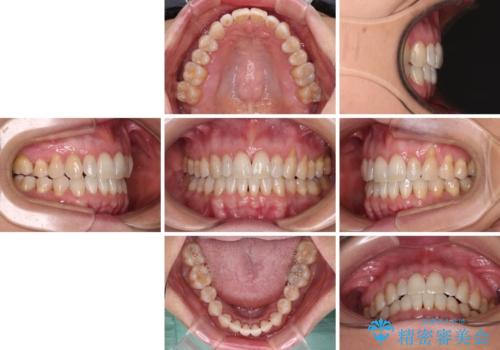

- 前歯の上下スペースによる食べにくさを気にして来院された患者様です。

インビザラインにより上下の前歯の隙間を閉じていくこととしました。

舌の突出癖があると上下前歯にスペースが開くため、矯正治療を機会に舌癖を改善するトレーニングを行ってもらい、矯正治療後の後戻りを防止するように指導しています。